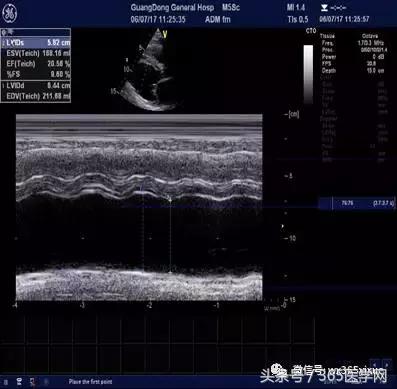

符合冠心病超声改变,左室收缩舒张功能减退(LVEF 31%),中度二尖瓣返流,轻度主动脉瓣返流,轻度三尖瓣返流,轻度肺高压。